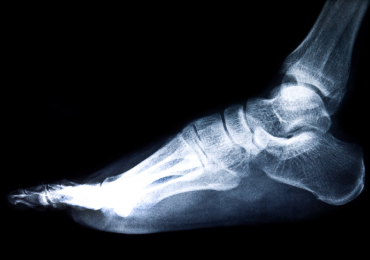

A heel spur is a calcium deposit causing a bony protrusion on the underside of the heel bone. On an X-ray, a heel spur can extend forward like a hook. Many calcaneal spurs are asymptomatic and pain usually comes with associated soft tissue inflammation.